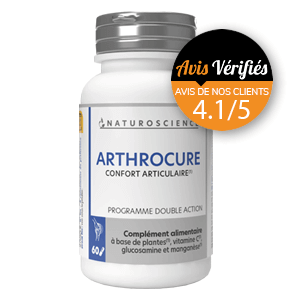

Conserver la souplesse de sa jeunesse est un rêve que caressent toutes celles et tous ceux qui souffrent de troubles articulaires. Entre les douleurs et les symptômes d’articulations grippées, les sorties deviennent difficile voire même risquées. En période de crise, chaque mouvement s’apparente à un supplice. Les prises successives d’anti inflammatoires apaisent ces douleurs un temps, mais ne sont pas sans conséquences sur le reste de l’organisme. Il existe pourtant des solutions naturelles qui calment ces épisodes douloureux et limitent la dégradation des cartilages.

Utilisées de manière ancestrales dans toutes les cultures du monde, certaines plantes, minéraux et autres micro organismes ont des effets notoires sur toutes les formes d’arthrose, sur la dégradation des cartilages et les douleurs inflammatoires.

Pour remédier à ces désagréments, certains compléments alimentaires enrichis en acide hyaluronique (substance naturellement présente dans l’organisme et qui assure la bonne motricité des articulations grâce à la qualité des cartilages) ou grâce à l’association judicieuse de certains extraits de plantes, permettent de conserver la motricité des doigts. Ces associations de plantes et de minéraux agissent directement sur la qualité du cartilage et évitent les inflammations et le gonflement des articulations.

Comme toutes les autres articulations, les vertèbres qui composent notre colonne vertébrale sont susceptibles de présenter des zones d’usure extrêmement douloureuses et invalidantes. Là encore, des compléments alimentaires pris judicieusement sous forme de cures régulières viennent relancer les processus naturels de renouvellement cellulaires. Le mal de dos ne doit plus être une fatalité. Grâce à l’avancée des recherches scientifiques et aux biotechnologies, on extrait le meilleur des plantes et des minéraux pour palier aux carences de l’organisme.

Malheureusement ces douleurs des genoux ne sont pas inhérentes qu’à l’âge. On les voit apparaître chez des sujets jeunes suite à des traumatismes répétés, du sport intense, une surcharge pondérale… Pour préserver le plus longtemps possible ses articulations du genou en bon état de fonctionnement, il ne faut pas hésiter à enrichir son alimentation de compléments alimentaires riches en acide hyaluronique, en vitamine D, en manganèse…